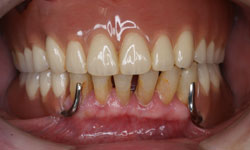

症例1: 入れ歯の症例

【治療前】